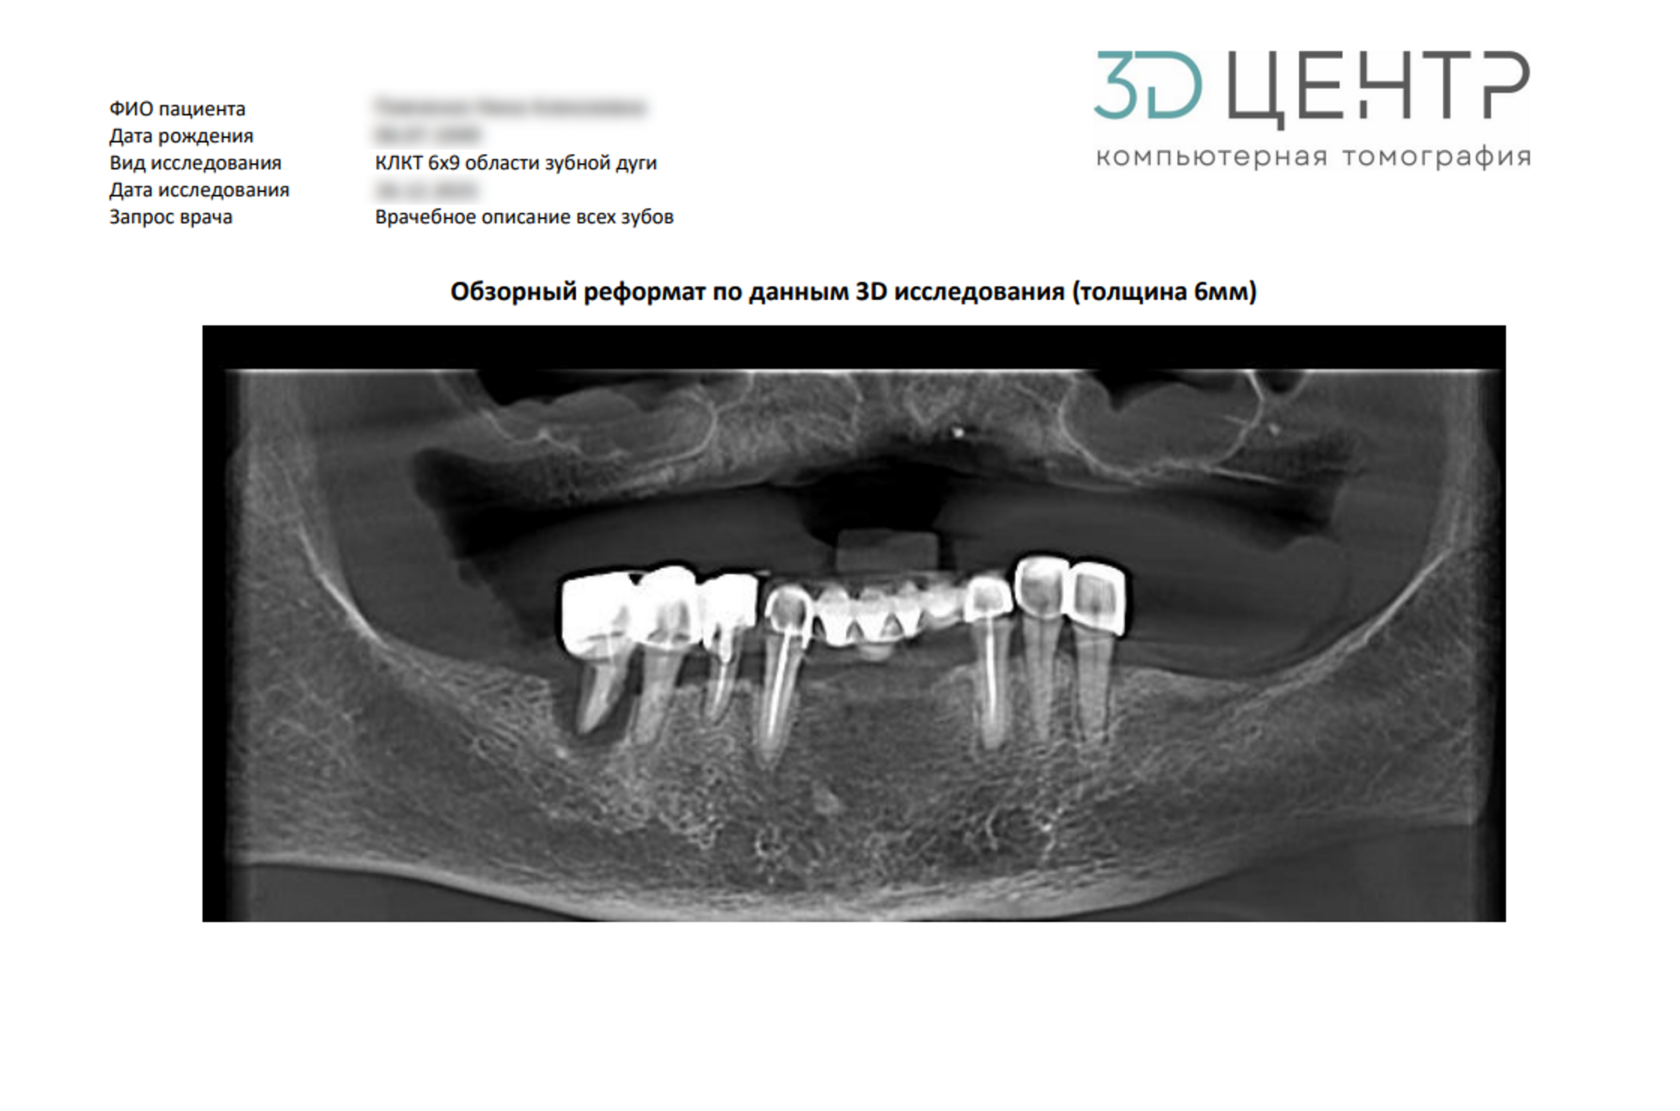

Двухмерный панорамный снимок зубов.